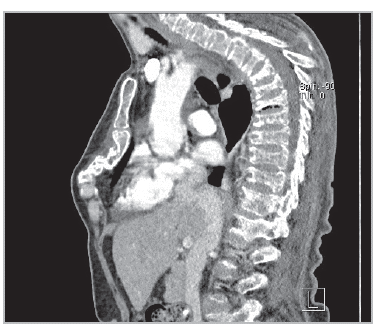

A 73-year-old woman with no relevant medical history began to experience accelerated loss of height (10 cm) over two months, with subsequent accentuated dorsal kyphosis and anterior chest deformity, which caused dyspnea and pain. On physical exam, the pectus excavatum was evident, with anterior protrusion of the distal segment, an occiput-wall distance of approximately 15 cm and a rib-pelvis distance of <1 fingerbreadth (Figure 1). The chest tomography showed multiple severe vertebral collapses with accentuated osteopenia and anterior chest deformity, due to sternal collapse, with no lytic lesions (Figure 2). The study of secondary causes confirmed an immunoglobulin G kappa myeloma.

Pathological sternal fractures are rare. In patients with multiple myeloma, they can lead to decreased quality of life due to hyperkyphotic deformity and sagittal malalignment, which increase the restriction, foster respiratory infections, cause pain and make it difficult to eat, due to the pressure exerted by the anterior ribcage on the stomach 1-2.